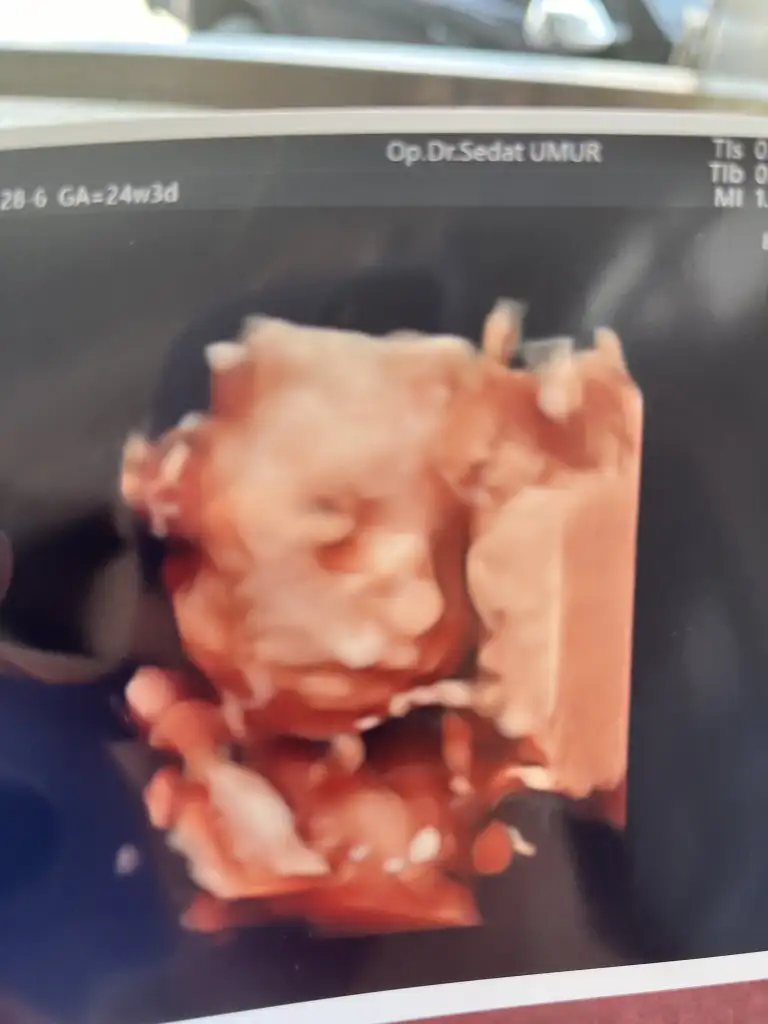

Selam canım anneler 😻😻 ben sonunda güzel haberler aldım . Sabahtan beri ağlıyordum . Devlet hastanelerinin canı cehenneme gerçekten . Özelde takipli olduğum doktoru da bırakıp özel bir kliniğe geçiş yaptım . Plasentam yukarı çıkmaya başlamış rahim ağzını kapamıyor bu gidişle normal doğum bile yapabilirsin dedi . Şekerim yokmuş sadece sağlıklı beslen dedi . Bebeğin suyu az demişlerdi buralar hep su içinde gayet yerinde dedi 😻😻 Allah’ıma şükürler olsun ki dünyalar benim oldu 🙏 kızının burnu aynı sen şişko dedi 😂😂😂 güzel kızım 33 cm olmuş 690 gram 🥲 Buda fotomuz teyseleriiii 😍